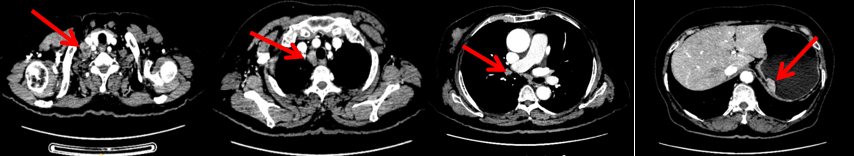

2024-11-5复查CT:右乳外上象限占位(11mm×9mm),较前明显缩小;上纵隔及右肺门多发淋巴结转移缩小;右锁骨上区淋巴结较前增大。余部位未见肿瘤转移及复发征象。

患者右锁骨上淋巴结肿大,需完善相关检查以进一步明确鳞状细胞癌的原发部位。

头颅+鼻咽部+颈部MR:右侧锁骨上区、所见上纵隔多发肿大淋巴结,考虑转移瘤。脑、鼻咽部未见明显异常。

患者右锁骨上淋巴结较前增大,乳腺病灶明显缩小,针对是否需要进行锁骨上淋巴结及乳腺手术,龚畅教授和曾银朵教授又组织了第三次多学科会诊。

影像科:CT显示右侧锁骨上区病灶增大主要表现为液化坏死改变,考虑为治疗后改变而非肿瘤进展所致。

乳腺外科:右乳肿物明显缩小,建议行右乳肿物切除术,可考虑同期行锁骨上淋巴结清扫术,以达到更好的局部治疗效果。

放疗科:建议行右侧下颈部区域行放射治疗。